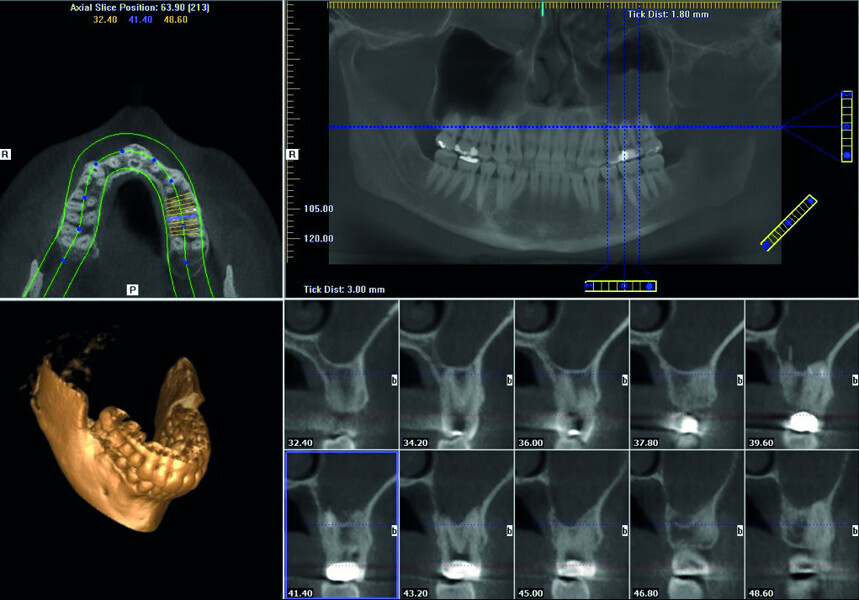

Maxillary sinus and root canal therapy complications